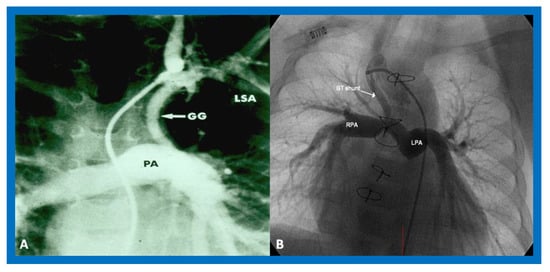

In patients with reduced PBF, the ductus arteriosus should be kept patent by intravenous infusion of prostaglandin E1 (PGE1) at a dose of 0.05–0.1 mcg/kg/min. After the O2 saturation gets better, the dose of PGE1 is slowly, stepwise, decreased to 0.02–0.025 mcg/kg/min to lessen the adverse effects of the prostaglandins. Subsequent to achieving a stable baby and studies needed to firm up the diagnosis, a more stable way of supplying the PBF should be undertaken. Several methods of augmenting PBF have been utilized in the past, as reviewed elsewhere [38]. Of these, modified Blalock–Taussig (BT) shunt [39], ductal stenting [22,40,41], balloon valvuloplasty of the pulmonary valve (if the major obstruction is at the level of pulmonary valve) [42,43,44], and most recently connection of the RV outflow tract with the PA via a non-valved Gore-Tex tube [45] are currently available options. However, most surgeons use a modified BT shunt by placing of a Gore-Tex graft between the subclavian artery and the PA on the same side [39] (Figure 9) to address pulmonary oligemia.

Figure 9.

Cine-angiograms demonstrating patent Gore-Tex grafts (GG) following modified Blalock-Taussig (BT) shunt surgery in two patients. Note wide-open BT shunts with good visualization of the pulmonary artery (PA) in (A) of the right (RPA) and left (LPA) pulmonary arteries in (B).